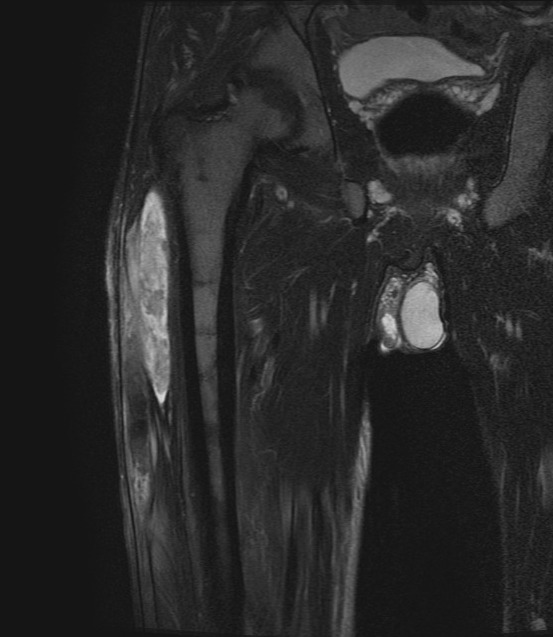

A 59-year-old man with Janus kinase-2 (JAK2) V617F mutation-positive polycythemia vera, evolving to myelofibrosis presented with a right thigh hematoma. Further evaluation showed prolonged activated partial thromboplastin time (aPTT), which was partially corrected after mixing with pooled normal plasma (PNP) and, low factor VIII (F VIII) levels. He was diagnosed to have acquired F VIII inhibitors, and treated with prednisolone for inhibitor eradication. After four weeks of treatment, his aPTT normalized, F VIII rose to 86% and the hematoma was resolved. The case report is followed by a discussion on the topic, revisiting the handful of cases published so far, and the possible mechanisms leading to inhibitor formation in MPN. Further studies are required to elucidate the pathophysiology and the incidence of F VIII inhibitor development in myeloproliferative neoplasms.